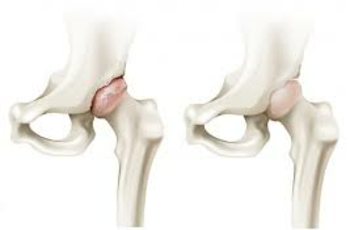

Протрузия

Углубление вертлужной впадины в тазовую полость, в сочетании с вхождением в нее головки бедренной кости называется протрузией. Подобная патология приводит к соударению всех костей таза во время движения. Трение разрушает хрящевую ткань и формируется артроз. Возникнуть протрузия может в результате остеопороза, рахита, коксартроза.

В начальной стадии заболевания может помочь физиотерапия, лечебная гимнастика. В более запущенных случаях может понадобиться хирургической вмешательство – остеотомия, эндопротезирование, резекция головки или шейки бедра.